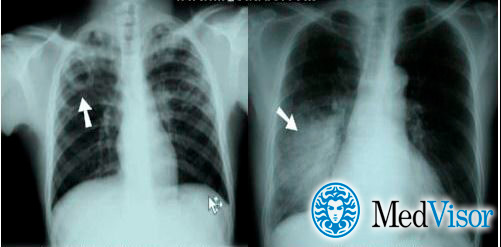

Отличия пневмонии от туберкулеза на рентгене

При пневмонии на рентгенограмме обычно видны инфильтраты и уплотнения. Типичное изображение представляет собой однородное или неоднородное белое пятно в основании пораженного легкого, либо в средней его трети. Типичным также считается плевральный выпот – скопление жидкости в плевральной полости – на той же стороне, что и очаг пневмонии.

Туберкулез обычно проявляется в виде кавитации (пустоты) в верхней части легкого. На снимке она выглядит как округлая полость. При этом также имеет место плевральный выпот.

Впрочем, отличия пневмонии от туберкулеза могут быть не такими очевидными как на снимке. Иными словами, одна флюорография не является показательной.

Рентген признаки при туберкулезе и пневмонии

Основной метод выявления туберкулеза – это флюорография. Но в некоторых случаях проводится и рентген легких. При пневмонии врачи предпочитают рентгеноскопию.

На снимке можно четко определить, в какой степени поражены легкие при туберкулезе и пневмонии, где локализуются очаги. Этот инструментальный метод диагностики подходит не только для взрослого пациента, но и для детей, которым до 15 лет делать флюорографию не рекомендуется.

Признаки на рентгене:

- При воспалении легких чаще поражается нижняя часть обоих легких. Тени, показывающие наличие очага при туберкулезе, расположены, как правило, в одном легком в верхнем или среднем сегменте.

- Очертания очагов поражений. Для пневмонии характерны размытые тени, пораженные легкие словно задымлены на определенных участках. При туберкулезе границы очагов очерчены, они имеют четкий контур на рентгеновских снимках.

Рентген

Рентгеновские снимки на сегодняшний день являются самым надежным методом в постановке диагноза заболеваний легких. Их поражение присутствует в обоих случаях, однако картина существенно различается.

Рассмотрим основные отличия этих заболеваний на снимках:

- Локализация поражений легочной ткани. При пневмонии инфильтративные тени, характеризующие очаги поражения, просматриваются, как правило, в 3, 4, 5, 7, 8, 9 долях легкого, преимущественно поражая нижние участки. Туберкулез, в свою очередь, имеет одностороннюю локализацию, в большинстве случаев поражая правую долю легких в 1, 2, 6 сегментах.

- Очертания теней. При пневмонии инфильтраты (рентгеновские тени) имеют размытые, нечеткие очертания. В острый период заболевания затемнение напоминает дымку, а по мере развития воспаления интенсивность теней возрастает, но нечеткий характер краев сохраняется. Туберкулез же имеет тени с выраженным четким рисунком.